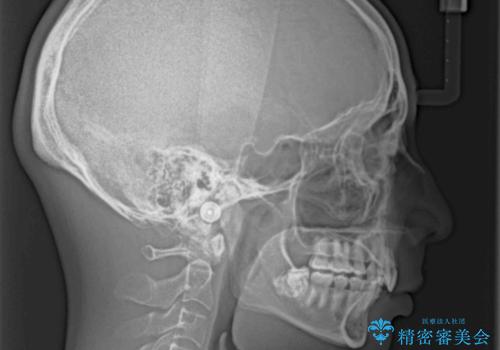

ディープバイトや奥歯の咬み合わせなど、インビザライン矯正では限界がありワイヤー装置での治療に及ばない仕上がりとなりました。

ただし、患者様としては八重歯や、それに伴う唇の閉じにくさが改善されたとのことで、納得いく状態での治療終了となりました。